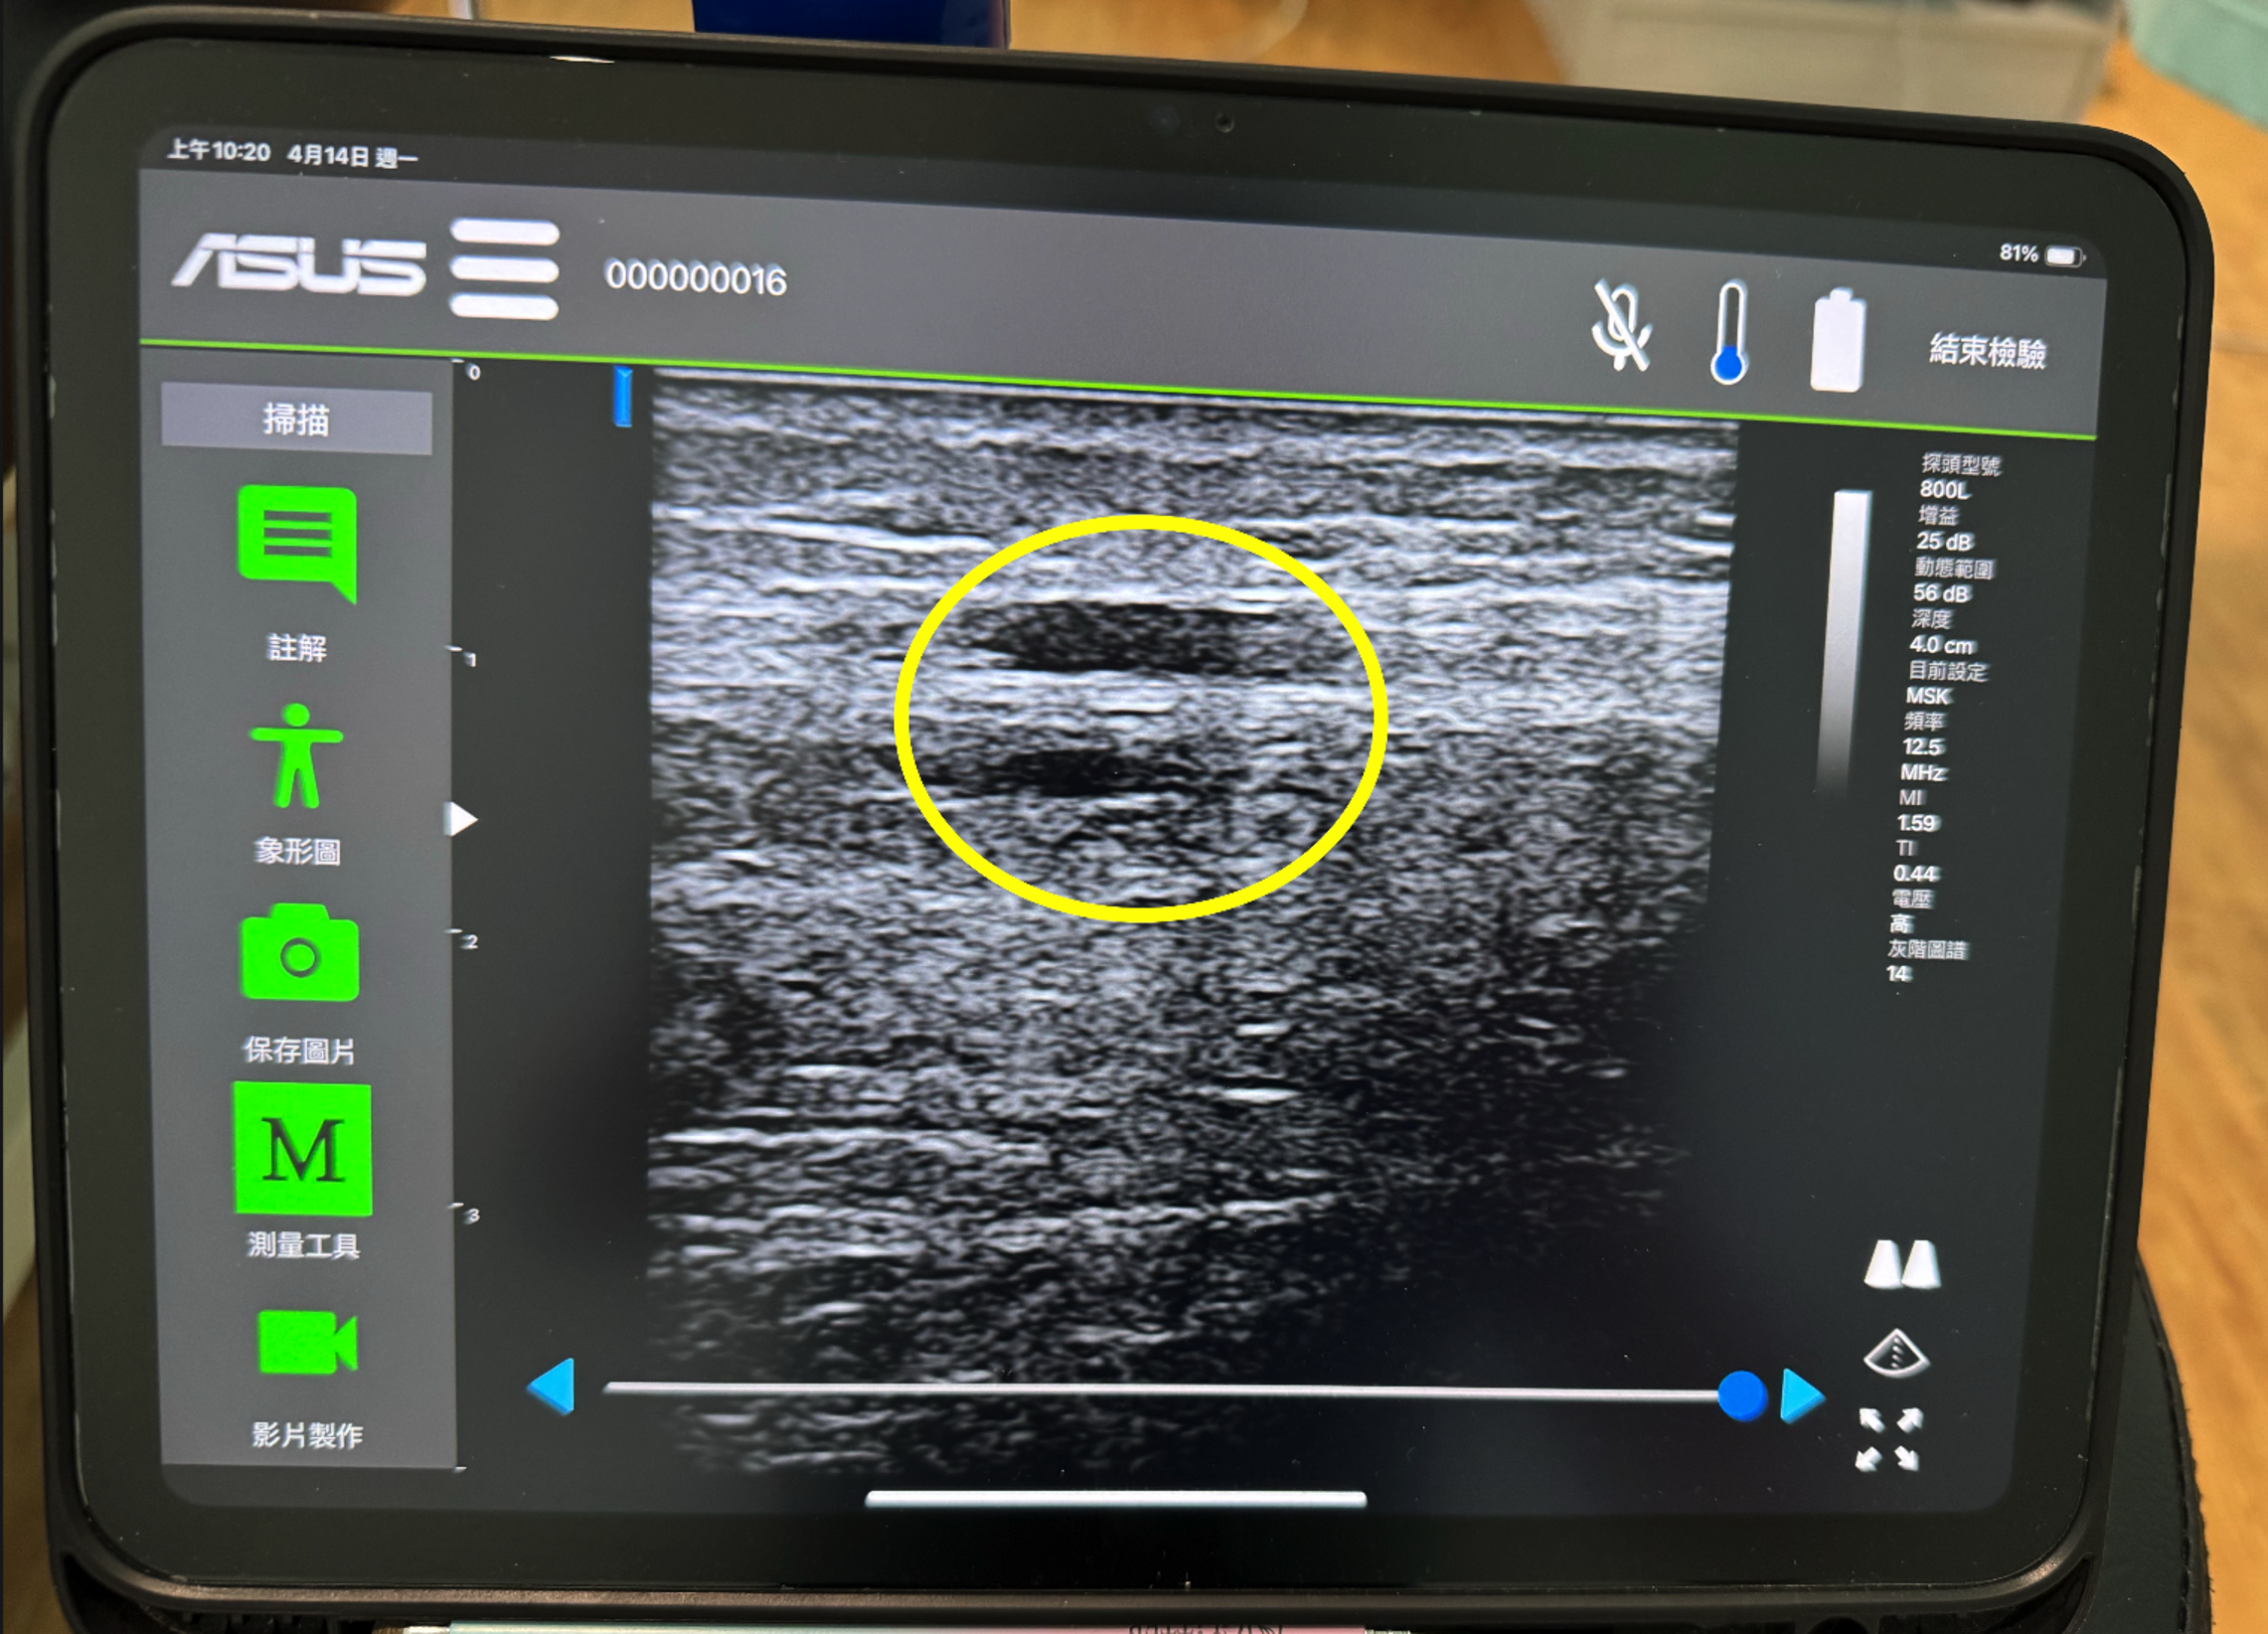

經由初步檢查與超音波檢查,我們發現朱先生的狀況如下:

(圖片來源:唯心運動物理治療所)